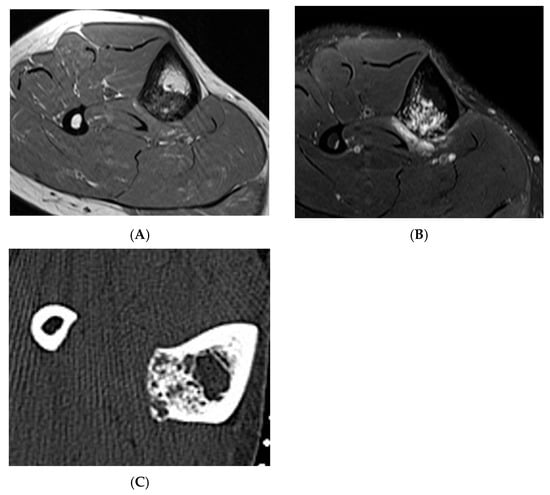

Figure 6.

Haemangioma, tibia. (A) Axial T1W MRI. (B) Axial STIR MRI. (C) Axial CT demonstrating “honeycomb” pattern of intraosseous haemangioma. Low signal intensity on T1 with corresponding high SIR signal on STIR suggests the low fat content of the lesion as seen on CT with few interspersed areas of hypodensity in the lesion.